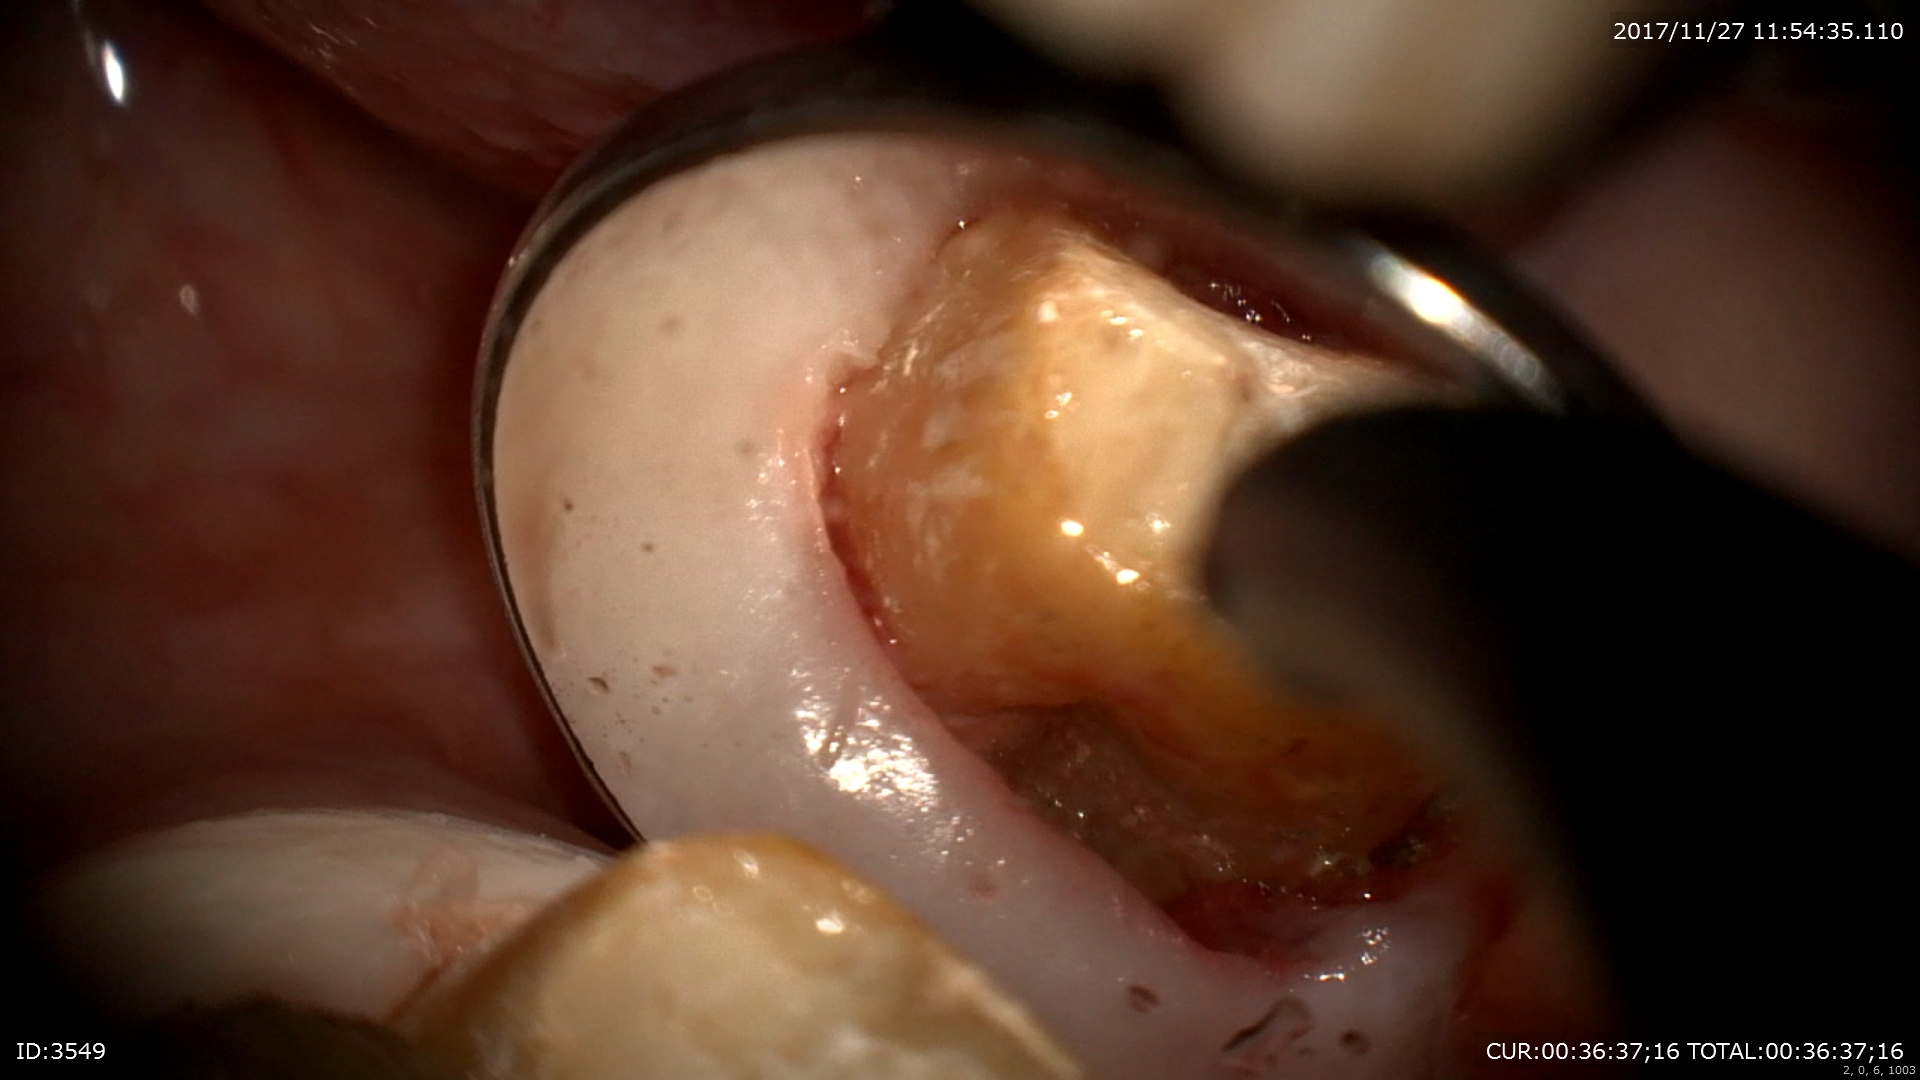

1ケース目ははるばる1時間以上かけていらして頂いている方の無痛歯周病治療

皆さまみえますか?歯と歯茎の境目にある黒くて岩みたいなものが歯石です。歯石は歯周病菌の塊です。歯周病菌の塊は歯石になっても毒素の作用が残ります。だから歯石は隅々まで取るべきだといわれています。しかしこの部位(上の一番奥の裏側)は見えません、だから一番奥の歯の歯のもちは良くないのですね。

そこでこのようにマイクロスコープを使用して無痛で取ります。

ここにも!!これは口臭の原因ともいわれています。歯周病菌は全身への影響やがんの発生率も上げるといわれています。

デブライドメントで綺麗に!

患者さまには終了後このような画面にして説明しました。とっても喜んで頂けて私も幸せ!